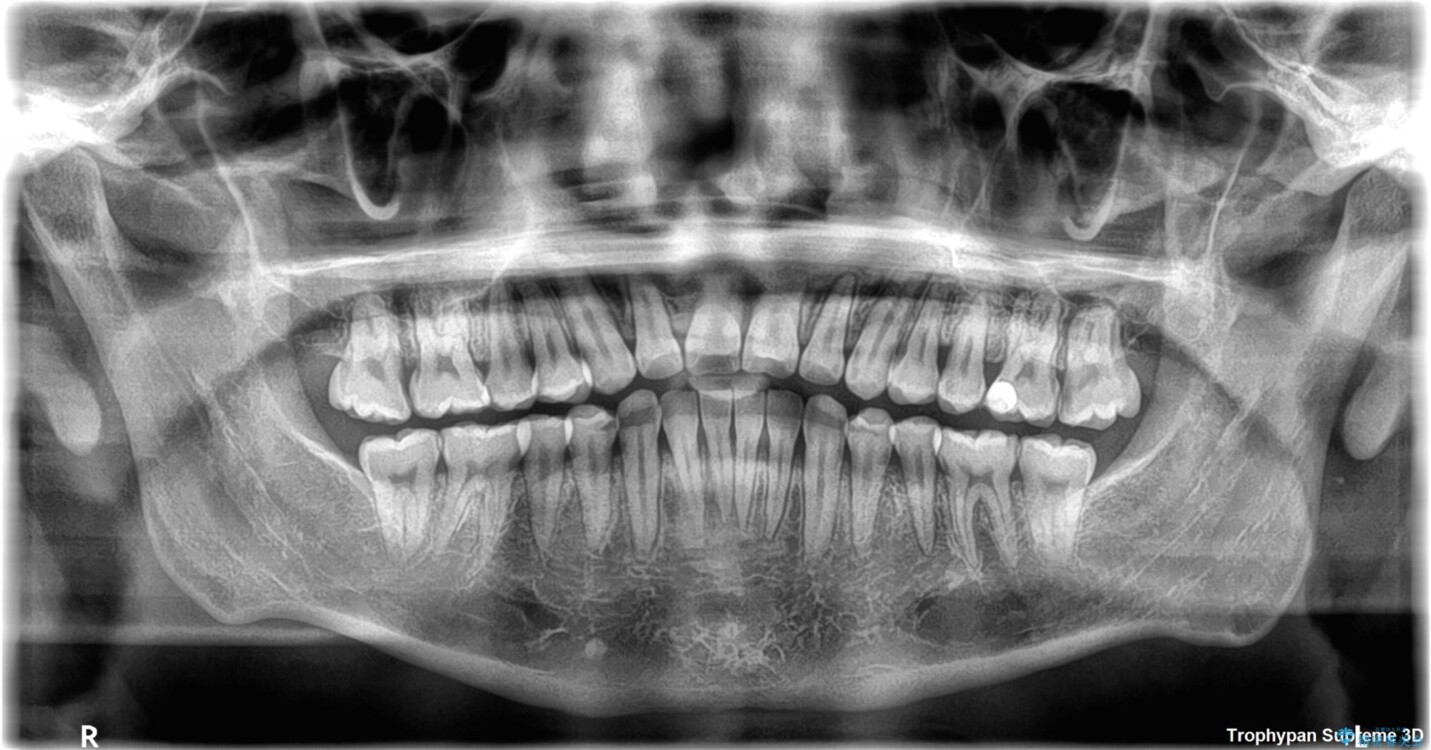

主訴:前歯のデコボコと奥歯のかみ合わせを治したい 今回ご紹介するのは、「前歯のガタガタ(叢生)」と「奥歯のかみ合わせ(シザーズバイト)」にお悩みでご来院された患者様の症例です。 患者様は、 ・歯並びをできるだけ早く改善したい ・費用を抑えた矯正治療 というご要望をお持ちでした。

・上顎左右の第二大臼歯が頬側へ転移し、シザーズバイト(scissors bite)の状態

・上顎左側第二小臼歯が90度捻転しており、噛み合わせに影響

治療前

• 前歯のガタガタ・奥歯のかみ合わせ(シザーズバイト)を改善|1年半で完了したメタルブラケット矯正 治療前画像